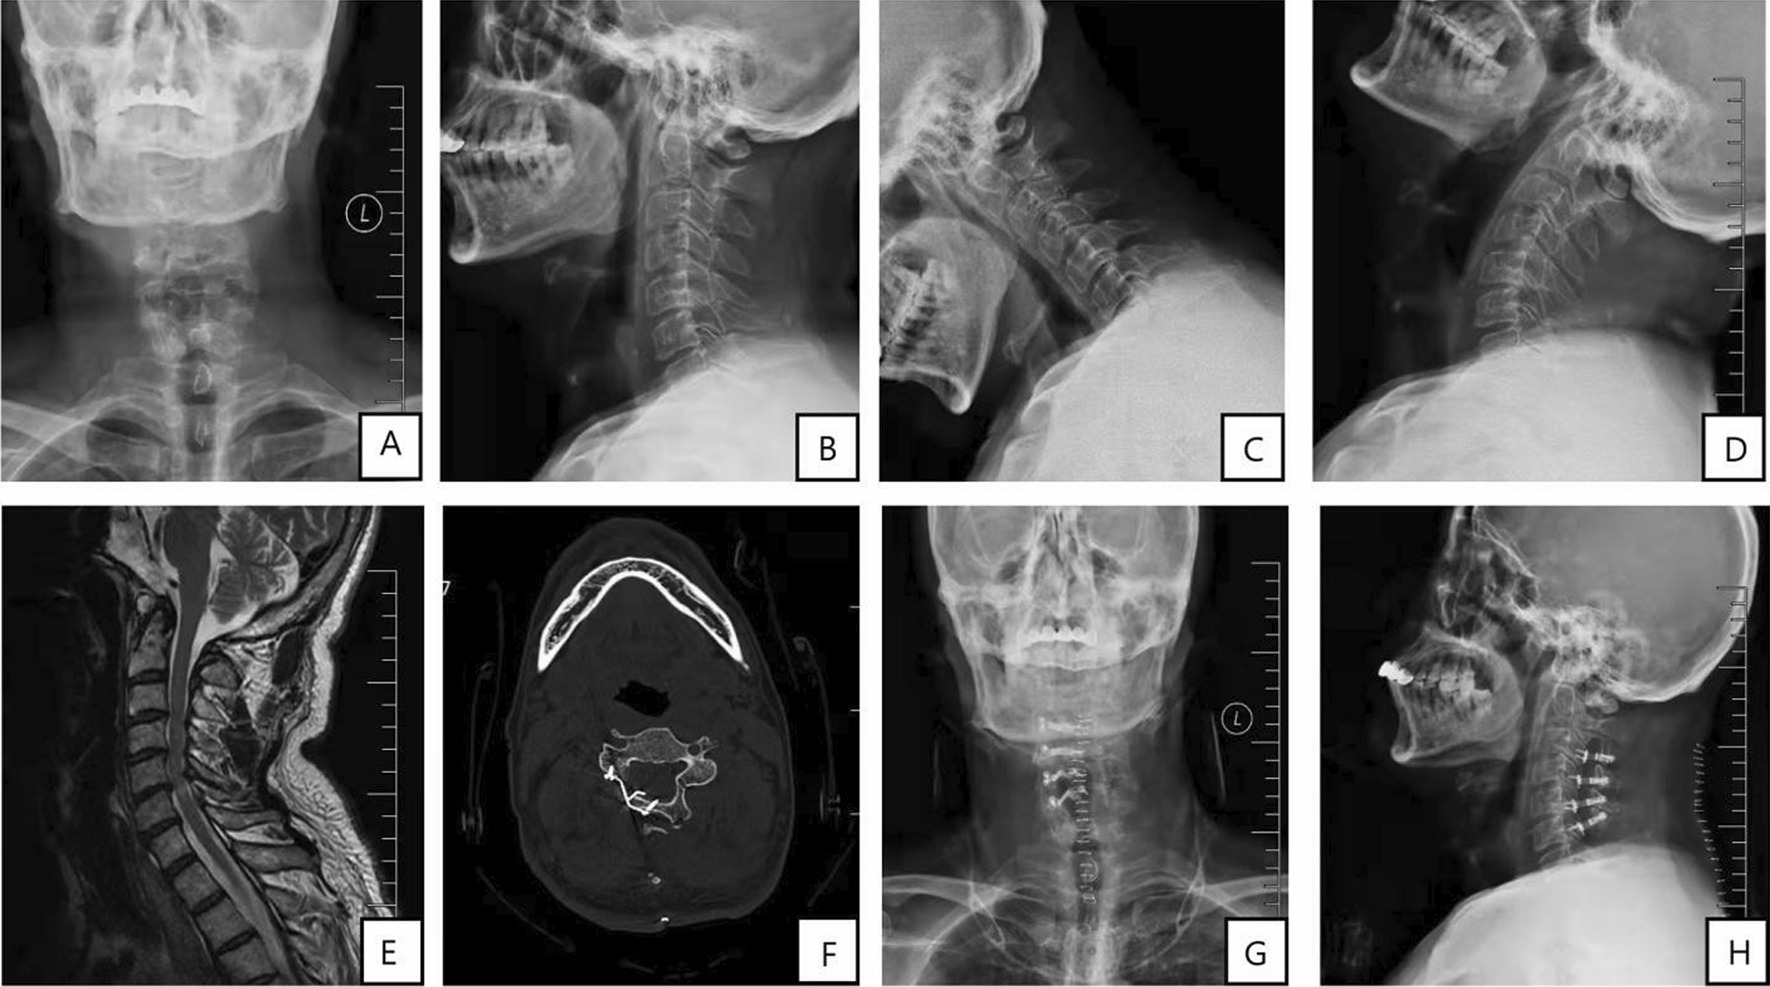

Fig. 1.

ACDF treatment for multisegments CS. A preoperative anteroposterior radiograph. B Preoperative lateral radiograph. C–D Preoperative hyperextension and flexion radiograph. E Preoperative cervical MR. F Preoperative incision. G Intraoperative incision. H Postoperative anteroposterior radiograph. I Postoperative lateral radiograph. J–L Postoperative CT and X-ray at the follow-up. M–N Postoperative hyperextension and flexion radiograph, and O postoperative incision